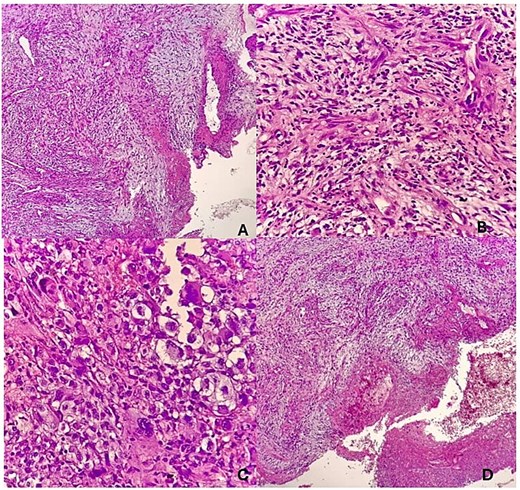

He presented to our facility with a 1-week history of spontaneous bleeding from a recurrent forehead swelling. There were associated palpitations, malaise, fever, anorexia, dizziness, and throbbing headaches. There was no altered mentation, loss of consciousness, or convulsions. On physical examination, he was alert, ill-appearing, and cachectic. He was afebrile with a pulse rate of 104 bpm and a blood pressure of 140/80 mmHg. There was moderate pallor with no lymphadenopathy, no clubbing, and no edema. There was a foul smelling, bicornuate, ulcerated forehead mass measuring 10 × 8 × 6 cm, with irregular borders. The mass was pink and friable with bleeding and areas of sloughing. It was soft with a smooth surface and no temperature gradient. There was tenderness to palpation with extension to the underlying bone (Fig. 1). A CT scan of the head was performed that demonstrated a frontal scalp mass with underlying invasion of the bone (Fig. 2).

CT scan of the head demonstrating a frontal forehead mass with extension to the underlying skull.